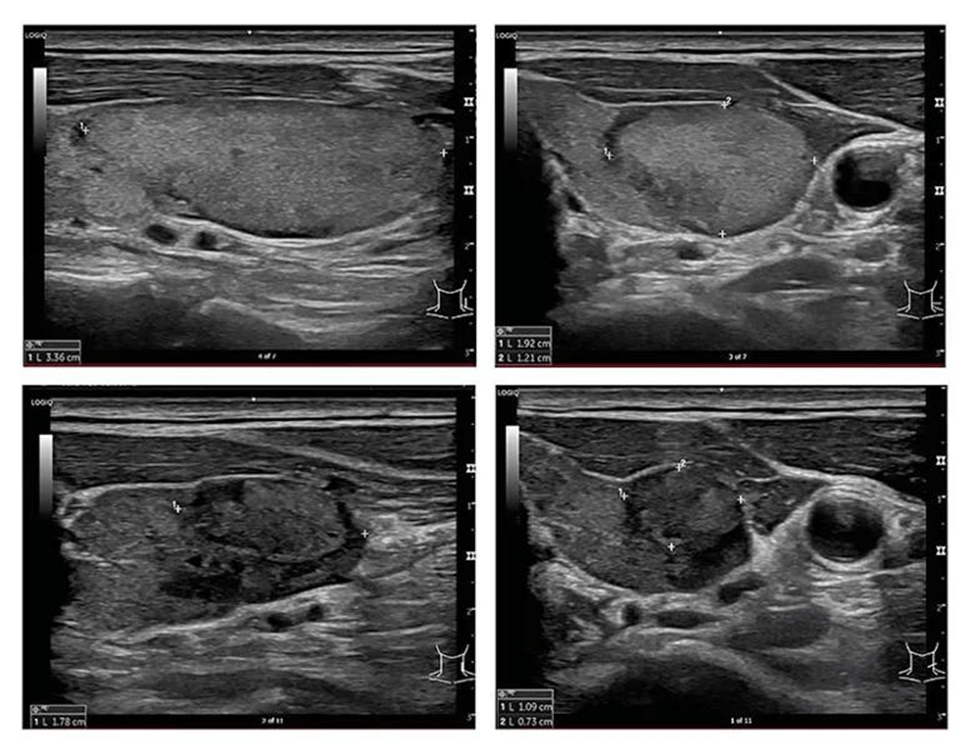

• Performed under ultrasound guidance

• Advanced ultrasound-guided FNAC